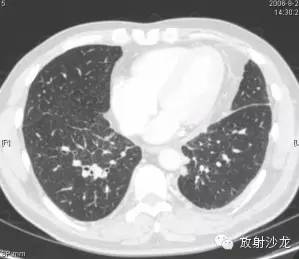

第三例:

51岁男性,体检发现肺门、纵隔、腹腔淋巴结肿大,CT拟诊结节病,后于北京协和医院确诊。

第1—3图显示Garland三联征。第4图显示腹腔淋巴结肿大。